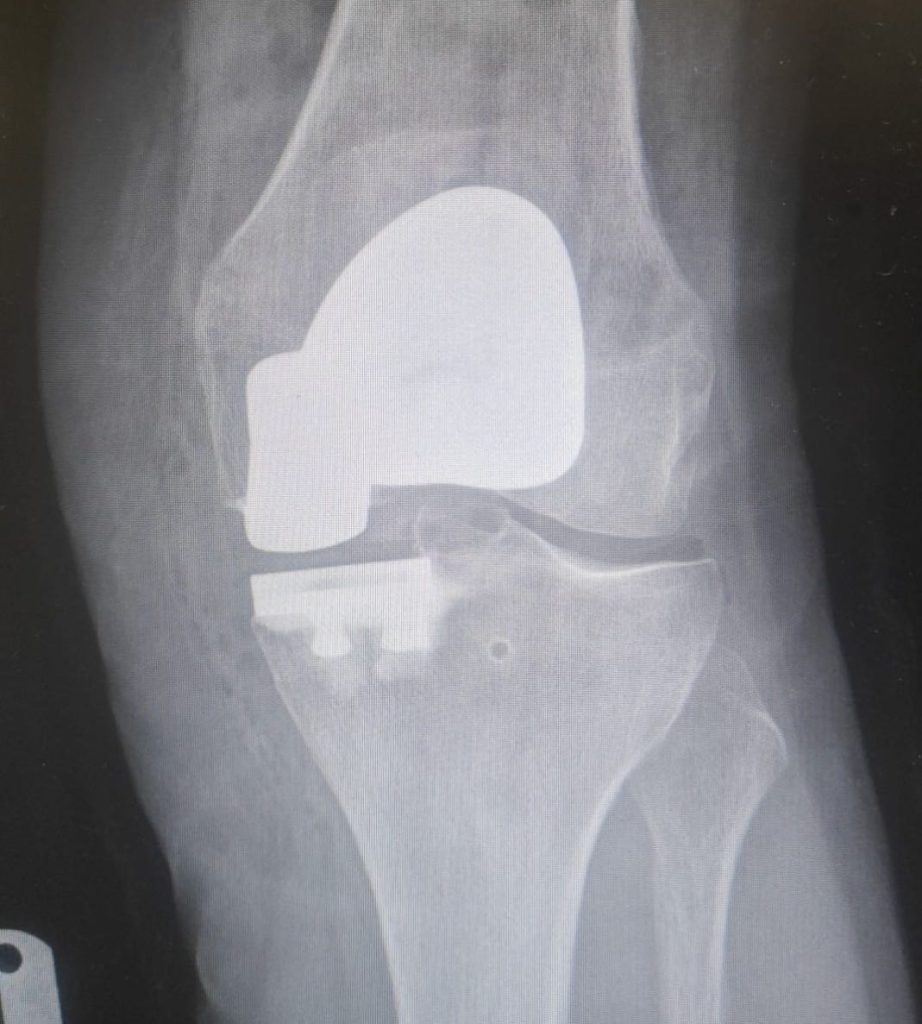

Mr Mughal is an experienced Consultant Orthopaedic Surgeon specialising in knee and hip surgery, with a particular focus on complex knee conditions and deformity correction. Born in Birmingham, he graduated in Medicine from Leeds University with Honours in Biochemistry and was awarded the prestigious William Macadam Prize in Medicine. He completed his surgical and specialist orthopaedic training in the West Midlands, followed by a dedicated Knee Fellowship in Derby, before being appointed as a Consultant at New Cross Hospital, Wolverhampton.

With more than 1,000 knee and hip replacements performed, Mr Mughal has extensive experience across all aspects of knee surgery. He has developed one of the largest specialist practices in the West Midlands for kneecap instability and has significant expertise in treating sports related knee injuries. His research includes publishing one of the world's largest series combining alignment and ligament surgery for recurrent kneecap dislocation, as well as widely adopted techniques for patellar realignment.

He performs a large number of partial knee replacements, many of which can be carried out as day case procedures. These minimally invasive operations typically allow faster recovery and now offer durability comparable to total knee replacement in suitable patients.

Knee surgery; Hip replacement surgery; Sports knee injuries; spinal pain; Sciatica; dislocating knee; knee deformity ; multi ligament surgery ; patella instability ; complex deformity surgery ; partial knee replacements ; unicompartmental knee replacement.